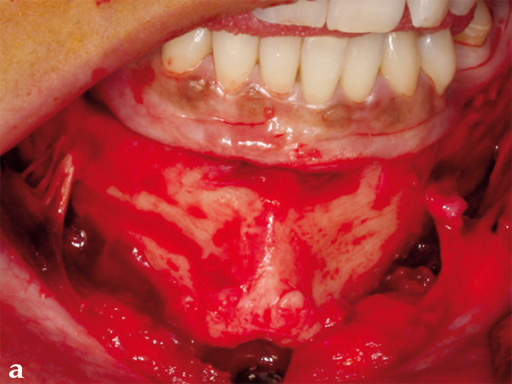

Case 1: A patient after multiple failed chin implants. Here piezosurgery proved to be superior to other oscillating instruments due to the controlled brush-type cutting motion, closeness to vulnerable structures which could be easily preserved, like the mental nerve on both sides, and protection of floor of the mouth vessels after completing the lingual corticotomy.

Case provided by Nils-Claudius Gellrich, Hannover, Germany